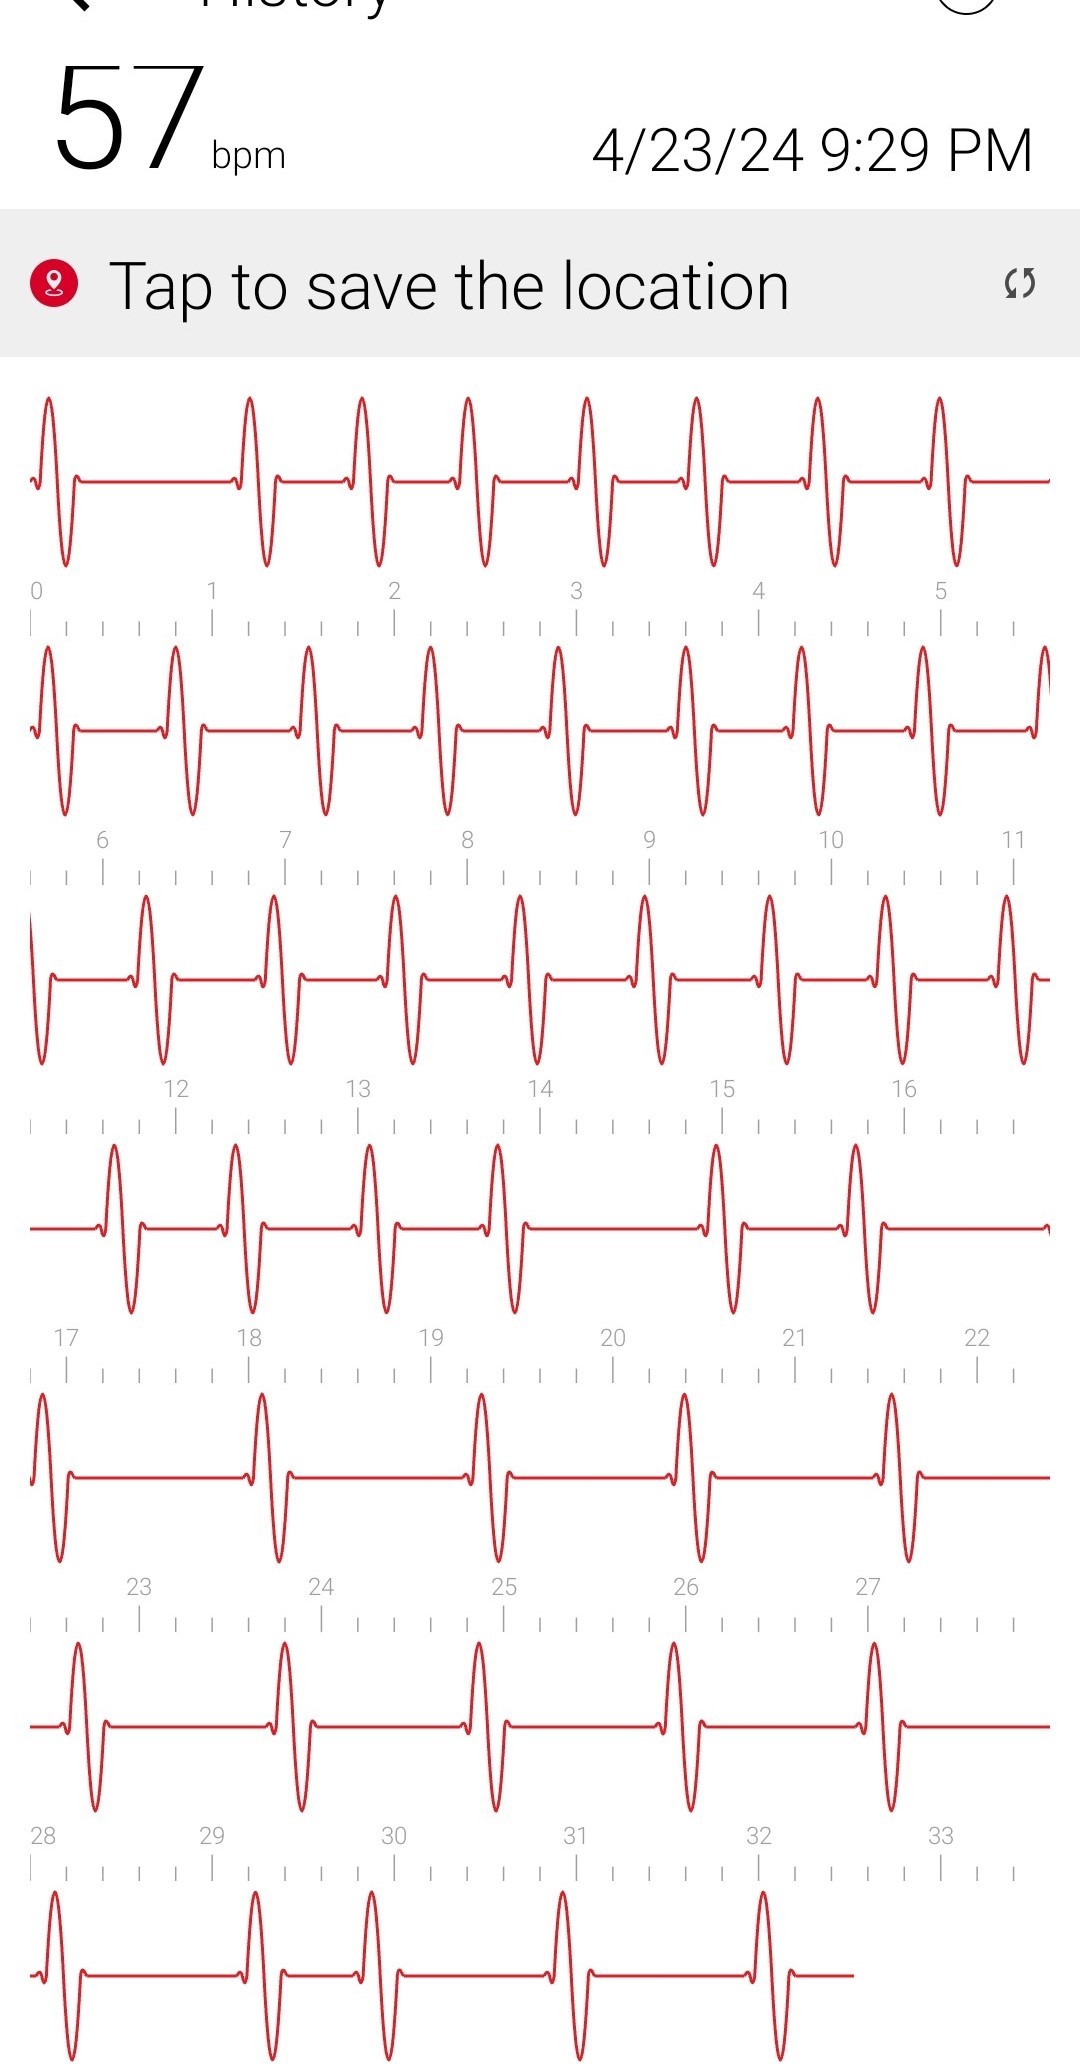

Initial ID consult diagnosed local tetanus based on clinical symptoms and recommended oral Metronidazole 500mg every 6 hours as an outpatient. Autonomic involvement developed with tachycardia and cardiac arrhythmia, along with episodes of sudden sweating. Loud noises made twitching/spasms worsen. Intermittent twitching continued to be present bilaterally in the body, face, jaw & tongue. Symptoms were suppressible with benzodiazepine. Tetanus IM IG 500 IU was recommended and obtained. After initial 2 week course of metronidazole was discontinued symptoms worsened again when patient would walk. Multiple trials of oral Metronidazole 500mg every 6 hours were attempted with some improvement while on the antibiotic but then return and worsening of symptoms again once antibiotic was discontinued.

incrementally, then once twitching had reached the spinal level, muscle twitching spread to the bilateral muscles of the body with cardiac arrhythmia & autonomic involvement/ sweating. A trial of antibiotic Keflex (cephalexin ) was suggested, which only at high dose (1000mg PO every 6 hours), helped keep spasms localized to the left foot mostly but symptoms would worsen and generalize if antibiotic Keflex (cephalexin) was stopped for more than 2 days. Benzodiazepine was increased to every q6 hours to reduce muscle twitching that had become constant in the left foot. Symptoms improve when patient does not walk or avoids any pressure or bending of left big toe and symptoms worsen when patient walks or stops antibiotic and has been unable to stop antibiotic for the past year and a half without worsening of symptoms. When antibiotic is stopped for 2 days bilateral jaws begin to snap shut intermittently involuntarily and cardiac arrhythmia/ heart block reoccurs. Symptoms worsen further after 4 days off antibiotic. Local

Oral Keflex (cephalexin) 1000mg 4 times a day & IM Bicillin LA 2.4 million units 3 times a week were restarted with improvement in bilateral body muscle twitching but twitching / spasms locally in the left toes and foot continued. This regimen was continued for 7 weeks. One day after discontinuing oral Keflex (cephalexin) (and 3 days after the last bicillin IM shot) spasms again began at the left big toe, left toes and left foot, progressed up the left leg to the left gluteal muscles and again once the spinal level was reached spasms spread to the right side of the body and then upper body and by 1 and 1/2 days after all antibiotic was discontinued, arrhythmia/heart block began again. Oral Keflex 1000mg 4 times a day was restarted (cephalexin). Benzodiazepines had been continued throughout.

Multiple attempts (>12) have been made to stop antibiotics, and consistently each time antibiotics are stopped the symptoms return. No cardiac abnormalities or symptoms of generalization are seen while patient remains on antibiotic. This presentation appears consistent with multiple case & data below which has demonstrated that in an immunized patient, tetanus toxin takes a retrograde neuronal route before reaching the CNS and generalizing since the blood bourne route is blocked by antibodies if immunized.

3) Cardiac Arrhythmia / Heart Block occurs during generalizations

When antibiotic is discontinued or with increased walking, rhythm returns to normal when antibiotic is restarted after a few days.